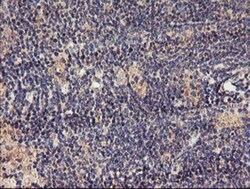

| Antigen | TMEFF2/Tomoregulin-2 |

| Applications | Western Blot, Immunohistochemistry, Immunohistochemistry (Paraffin) |

| Dilution | Western Blot 1:500-2000, Immunohistochemistry 1:150, Immunohistochemistry-Paraffin 1:150 |